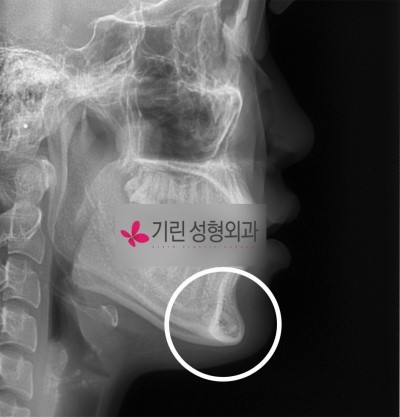

앞턱길이를 줄인 경우. 수술전엑스레이

![턱의 길이를 줄여주는 턱끝수술[앞턱길이줄임술] 관련 이미지 3](https://pub-9f2bb3498faf4d1d8714b41df24753e3.r2.dev/content/clinics/archive/pr7y376obf/naver_blog/girinlife/assets/by_hash/8762bc8772e87cf60b057ca5d8897d3e39bd3781df1e2bdfa3b98273ab4581c5.jpg)